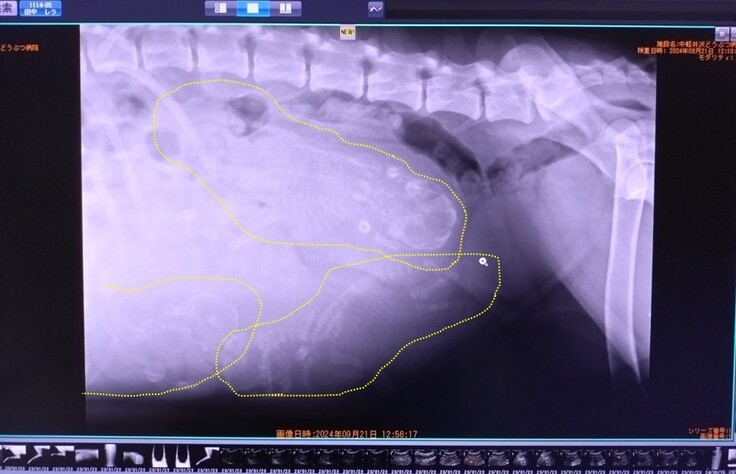

さて、昨日はかかりつけの動物病院で、レントゲンによる胎児頭数の確認の検査にも行きました。

検査の結果、レラの子犬は 3頭(黄色い破線部が胎児) 。

通常、アメリカのベアドッグ育成団体での一腹の平均産子数が6~7頭ですので、少なめの出産となりそうです。

少ないから安産?と思いそうですが、実はお腹の中で(スペースがたくさんあるので)胎児が大きくなりすぎ、難産になることがあるとのこと。かかりつけの先生からは、「万が一のときは夜でも連絡をください」と言われています。

レントゲン検査での胎児の頭骨幅の計測値は4.1cm。

すでに生まれるには十分の大きさです。